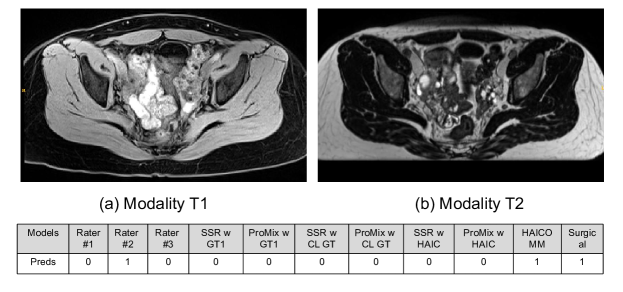

We also conduct qualitative analyses about HAICOMM. In Figure 2, (a) and (b) are the input T1 and T2 MRIs, respectively. The table below shows the predictions by the three raters (Rater #1,#2,#3), then the predictions by SSR and ProMix trained with Rater #1’s labels and CROWDLAB’s labels (SSR w GT1, ProMix w GT1, SSR w CL GT, ProMix w CL GT). Next, we show SSR and ProMix trained with CROWDLAB’s labels and relying on human-AI collaborative classification (SSR w HAIC, ProMix w HAIC), followed by the result from our HAICOMM, and the ground truth label from surgical data. The case shows the proposed HAICOMM model can generate correct labels while other models cannot. For Figure 3, the case also shows that the proposed HAICOMM model can generate a correct label while most other methods cannot (only ProMix w GT1 and HAICOMM predict the surgical ground truth label correctly).

Figure 3: Another qualitative example analysis of HAICOMM.